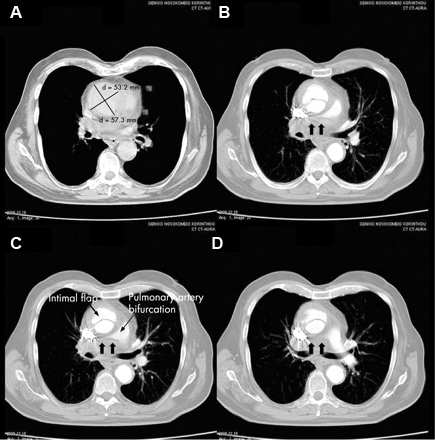

Aortic dissection

Aortic dissection more commonly affects middle-aged and older men, those with pre-existing valvular heart disease (such as bi-leaflet aortic valve or coarctation of the aorta), and patients with collagen disorders (such as Marfan syndrome or Ehlers-Danlos syndrome). It typically presents with dyspnoea and severe chest pain that may radiate to the back. It may be accompanied by hypotension. Examination of the peripheral vascular system may demonstrate absent peripheral pulses, or differences in blood pressure measurements between upper and lower extremities.

Ascending aortic dissection should be suspected with widening of the mediastinum on chest x-ray, although this sign is only present in about 50% of patients.[69] Emergency echocardiogram or CT chest angiography is used to confirm diagnosis.[Figure caption and citation for the preceding image starts]: CT of a 71-year-old man showing type II dissecting aneurysm of the ascending aorta. Haematoma around the proximal segment of the ascending aorta (panels A-D) compressed the right pulmonary artery, almost occluding its patency and limiting the perfusion of the reciprocal lungStougiannos PN, Mytas DZ, Pyrgakis VN. The changing faces of aortic dissection: an unusual presentation mimicking pulmonary embolism. BMJ Case Reports 2009; doi:10.1136/bcr.2006.104414 [Citation ends].

Management of aortic dissection depends on the site of dissection. While type A (ascending aortic) dissections constitute a surgical emergency, type B (descending aortic) dissections are initially treated medically. Surgical intervention in type B dissection is reserved for those who do not respond to medical management. Endovascular treatment options are gaining popularity in the initial management of type B dissections.[70][71]